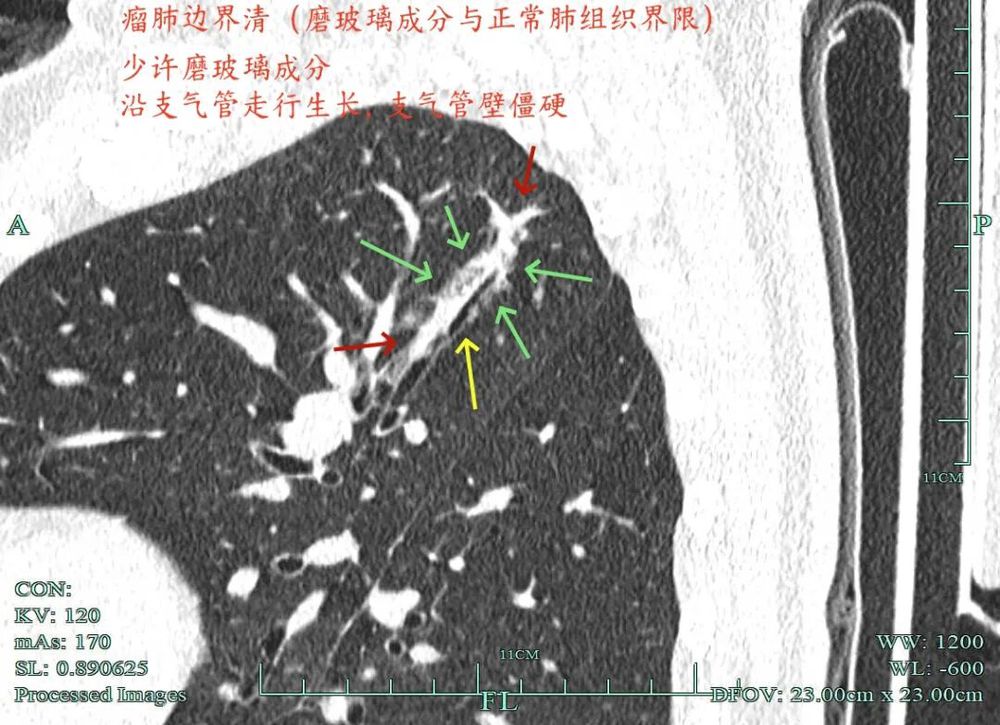

影像展示与分析:

杭州市肿瘤医院影像展示与分析:

右上也有混合密度结节,实性部分缺乏膨胀性与收缩力,磨玻璃成分较淡,也偏糊,但持续存在仍得考虑肿瘤范畴可能性大。

此视角是混合密度,实性为主,贴胸膜近。

今天这位结友的病理类型稍差于术前的预测,但从其三年多随访情况来看,进展不算大厉害,第10组与第12组淋巴结均阴性的话,还是真早期的可能性还是较大的。后续倾向暂随访观察,可以采取相对稍积极的随访策略,比如两年内4个月复查一次,三到五年内半年复查一次,五年后再年度复查;而且右侧的病灶要在随访进展或身体恢复良好后微创局部楔形切除。期间万一有转移,其实是伪早期的话,则基因检测并全身性治疗。其实今天这种病灶在临床中被判断为炎性的并不少见,尤其是非胸外科医生。因为胸外科的一般相对积极,警惕性高些。在我的公众号上其实也分享过多例这种看着似乎是炎性,但长时间随访不好转,或缓慢进展的病灶其实是浸润性腺癌的一种特殊表现,不少见的。我感觉此类病灶比较主要的临床特征是:1、密度多是混合磨玻璃密度,实性成分较明显,磨玻璃成分较淡,病灶显得密度较为杂乱不均;2、整体形态膨胀性不明显,收缩力不太强;3、灶内支气管通气及显得较为僵硬,血管征不典型,但表面多是不平不规则,较为毛糙,分叶多可见;4、随访或抗炎治疗不好转,进展不快,相对较为缓慢。容易被人以为是慢性炎症。但此时我们要注意几点:1、寻找磨玻璃成分,并观察瘤肺边界,尤其是磨玻璃成分与周围正常肺组织之间的界限是否清楚,清楚的多是恶性;2、靶重建从不同角度观察病灶形态,看病灶与邻近结构的关系,有无推压、破坏或支气管截断等征象;3观察病灶内部通气支气管的形态,扭曲、僵硬不舒展的多容易是恶性病变。总体上,要对“影像看着像慢性炎,但随访持续存在且有磨玻璃成分的”病灶要特别提高警惕,对于靠近边缘部分的,手术创伤不大的,要考虑“开刀带来创伤与随访导致的风险”之间的利弊权衡。我的根本理念仍是:淡化最后病理结果,从风险角度考虑问题!